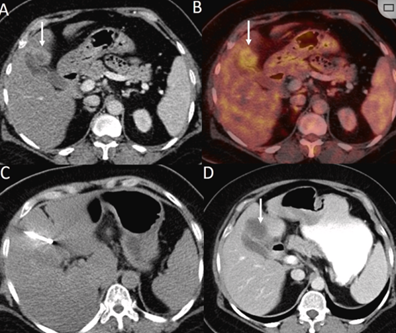

CT引導(dǎo)的冷凍消融

(a) 射頻消融后在病變邊緣顯示殘余增強(qiáng)。(b) 冷凍消融術(shù)中影像顯示冰球完全覆蓋病變。(c) 19個(gè)月后隨訪,沒有發(fā)生局部腫瘤進(jìn)展。完全消融率為97%(66/68);2名患者均接受了額外的冷凍消融,隨后實(shí)現(xiàn)完全消融。平均隨訪期為 12.8 個(gè)月(范圍:3-27 個(gè)月)。所有患者均接受影像復(fù)查(CT 或 MRI)。11個(gè)病灶(16.2%)檢測到局部腫瘤進(jìn)展,6、12和18個(gè)月時(shí)的累積局部腫瘤進(jìn)展率分別為4%、8.2%和20.5%。8例出現(xiàn)遠(yuǎn)處肝內(nèi)或肝外病變的患者接受經(jīng)動脈化療栓塞、經(jīng)動脈化療栓塞加射頻消融治療或全身化療。

主要和次要并發(fā)癥發(fā)生率分別為3.5%(2/57)和22.8%(13/57)。并發(fā)癥主要表現(xiàn)為局部皮膚凍傷、中度氣胸、發(fā)熱,僅有少數(shù)患者接受治療,多數(shù)患者自行恢復(fù)。所有患者能耐受圍手術(shù)期疼痛,VAS 評分范圍在 1-3 分之間(平均 1.65分)。3例患者術(shù)后疼痛加重,VAS評分達(dá)到4~5分,患者口服止痛藥后逐漸緩解。所有患者術(shù)后1天血常規(guī)、白細(xì)胞計(jì)數(shù)均升高,血小板均有不同程度下降,但變化值均在正常范圍內(nèi)。肝功能1個(gè)月后逐漸恢復(fù)到正常水平。